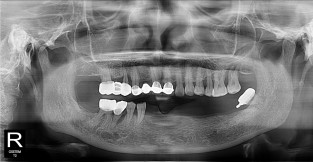

무치악

치료기간 : 2023-02-21 ~ 2023-10-21

1. 상기 x-ray 이미지 모두 동일한 해당 의료기관에서 진료한 환자입니다.

2. 상기 x-ray 이미지 모두 동일 인물의 것입니다.

3. 치료 전 이미지는 2023-02-21에 촬영했으며, 치료 후 이미지는 2023-10-21에 촬영하였습니다.

4. 상기 x-ray 이미지 모두 동일 조건에서 환자분의 동의를 받아촬영되었습니다.

* 임플란트 시술은 환자분의 상태(고혈압, 당뇨 등)에 따라 부작용이 있을 수 있으니, 반드시 전문의와 상담이 필요합니다.

* 임플란트 수술 부작용

: 수술 후 출혈, 교합, 통증, 붓기, 염증 등의 문제점이 발생할 수 있습니다.)